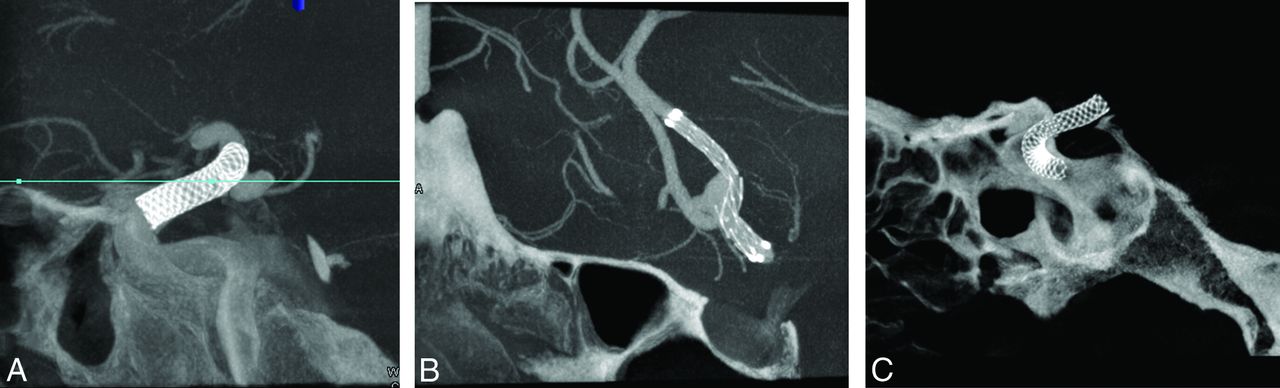

Excellent visibility of stents and flow-diverter devices was noted in the VOI C-arm CT images in all 28 patients, acquired both with and without contrast medium injection (Fig 2). Stent expansion, wall apposition, and neck coverage were depicted clearly in the VOI C-arm CT images reconstructed with the ATRACT robust reconstruction algorithm. VOI C-arm CT images from conventional FDK reconstructions have severe truncation artifacts, resulting in capping/cupping artifacts and a substantial offset in Hounsfield unit values as seen in Fig 3B. These truncation artifacts were greatly reduced with the ATRACT reconstruction (Fig 3C).

Sample cross-sections from the ATRACT reconstruction of VOI C-arm CT images from the patient cohort. VOI images show clear visibility of stent and flow-diverter devices and their relationship with the parent artery.

A 58-year-old woman who presented with a basilar tip bifurcation aneurysm was treated with stents and coils (Fig 6). A noncollimated full-head C-arm CT acquisition (20-second DynaCT protocol) was performed to examine the brain parenchyma immediately after the stent was deployed. Additionally, a 20-second VOI C-arm CT was acquired with dilute contrast injection (injection protocol given above) to study the relationship of the device with the parent artery. Figure 6B shows the ATRACT reconstruction of the VOI acquisition. The stent deployed into the right posterior cerebral artery was well-apposed and provided good neck coverage, thus avoiding a need to deploy a second stent into the left posterior cerebral artery. Furthermore, the stent was manually delineated from the 3D images and overlaid on the live fluoroscopic images for assistance during coiling (Fig 6C). A 91.7% reduction in DAP values was achieved in this example with the VOI C-arm CT acquisition.

VOI C-arm CT images of a basilar tip aneurysm in a 58-year-old woman treated with stent and coils. Contrast-enhanced VOI C-arm CT images were acquired immediately after the stent was deployed. A, Frontal projection of a VOI C-arm CT acquisition. B, ATRACT reconstruction of the same VOI C-arm CT. C, Fluoroscopic overlay of the stent for assistance during coiling. Note that the high-contrast objects like stents are well-visualized with the VOI C-arm CT images. In this particular example, based on the C-arm CT imaging neck coverage was good after the deployment for first stent from the right side, thus avoiding the need for a second stent.